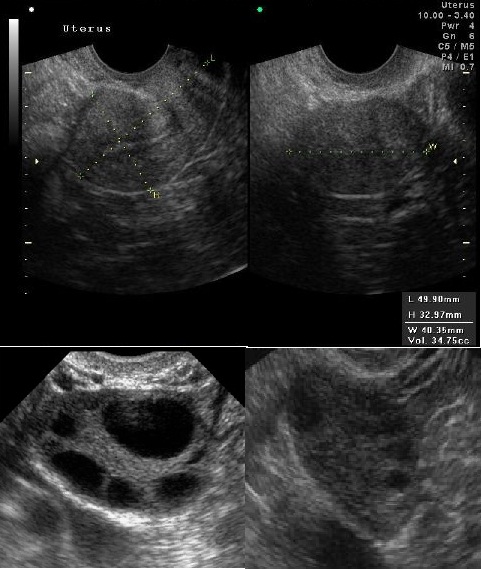

BeSt programmi toetusel valminud õpiobjekt "Korduv raseduse katkemine" on koostatud eesmärgiga anda sünnitusabi ja günekoloogia eriala spetsialistele, doktorantidele ja residentidele kaasajastatud ülevaade igapäevases kliinilises töös suhteliselt sageli esinevast probleemist. Õppematerjal koosneb nelja haigusjuhu analüüsist ja teoreetilisest osast, kus käsitletakse korduva raseduse riskitegureid, põhjusi ja ravi võimalusi. Õppematerjal sisaldab mitmeid testivormis küsimusi, mille abil saab hinnata oma teadmisi õppeprotsessi vältel. Kasutatud materjalid ja täiendavad infoallikad on toodud materjali lõpus teemade kaupa. Õppematerjali läbitöötamiseks kulub orienteeruvalt 10-12 tundi.